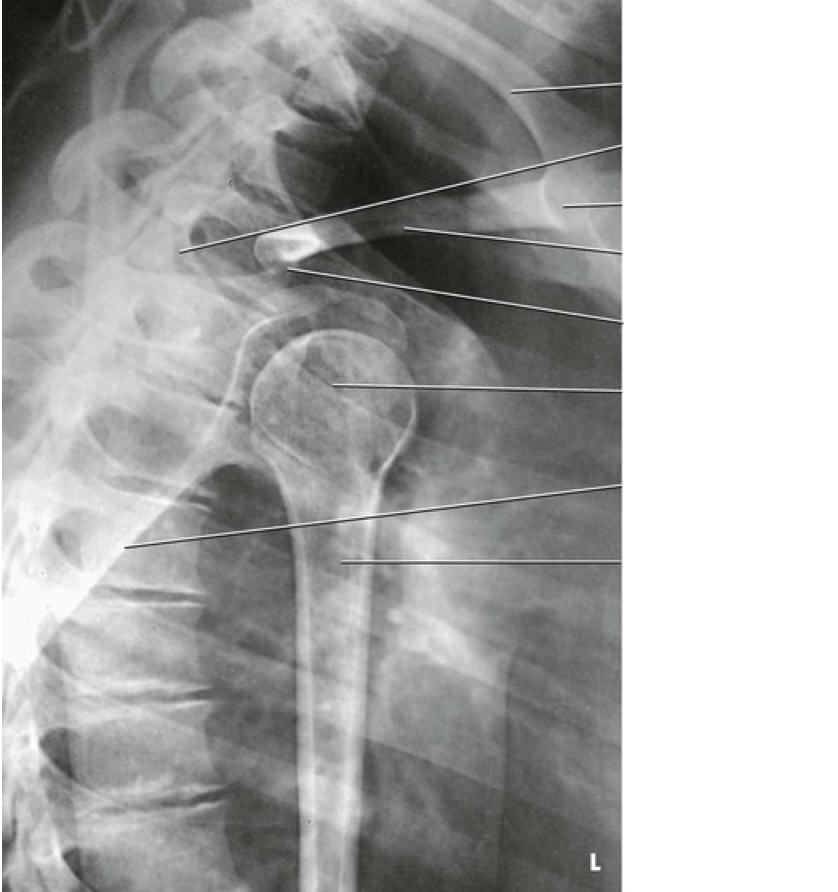

Question 11

Question

Label the image

Image:

b2b11331-4770-43e9-a0ed-661e02d896b7 (image/png)

Answer

unaffected clavicle

scapula (superior border)

sternum

clavicle

acromion process

humeral head

scapula (lateral border)

proximal humerus